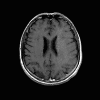

Neurologic and mental examination showed intact immediate memory but inability to recall 3 objects in 5 minutes. He was not oriented to time or space or situation but oriented to person. His remote memory was intact. There was left superior quadrantonopsia but no focal motor or sensory deficits. FLAIR images on MRI showed a lesion in the left mesial temporal lobe (Panel 1). This lesion had increased T2 signal but without enhancement on T1 images. This lesion also had mass-effect and edema within that region. On FLAIR images, there were some small foci of abnormal signal in the white matter of the right parietal lobe (Panel 2) but these foci did not enhance (Panel 3). There is a vague, poorly demarcated, triangular shaped periventricular signal abnormality in the left parietal lobe (Panel 2) but this area did not enhance (Panel 3). On another image (obtained higher to Panel 2 and 3), however, there is a small cluster of enhancing spotty signal in the white matter of the left parietal lobe (Panel 4) and the largest focus is about 0.4 cm in diameter. There were areas with features of encephalomalacia in his right mesial temporal lobe that would be explained by his history of prior infarct.

4. T1+Contrast |